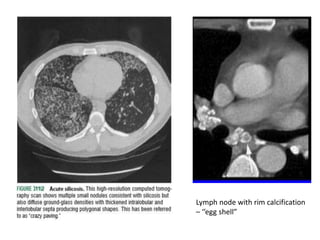

Silicosis- occupational lung disease

• CXR- diffuse miliary or nodular pattern in upper and

• CT scan – characteristic “crazy-paving” pattern

Lymph node with rim calcification

– ‘’egg shell”

Silicosis- occupational lungdisease • Grinder’s disease • Inhalation of silica particles ( crystalline forms are most fibrogenic)- engulfed by macrophages- release cytokines for fibroblast proliferation and collagen deposition. • asso. with increased susceptibility to TB due to CMI • Assymptomatic or present –proggressive dyspnoea, cough and pleuritic pain • CXR- diffuse miliary or nodular pattern in upper and mid zones, egg-shell calcification of hilar nodes • CT scan – characteristic “crazy-paving” pattern

Lymph node withrim calcification – ‘’egg shell”